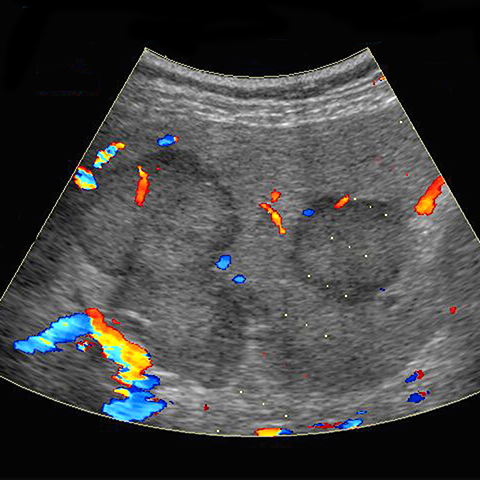

Liver metastases, color doppler ultrasound [3 of 3]